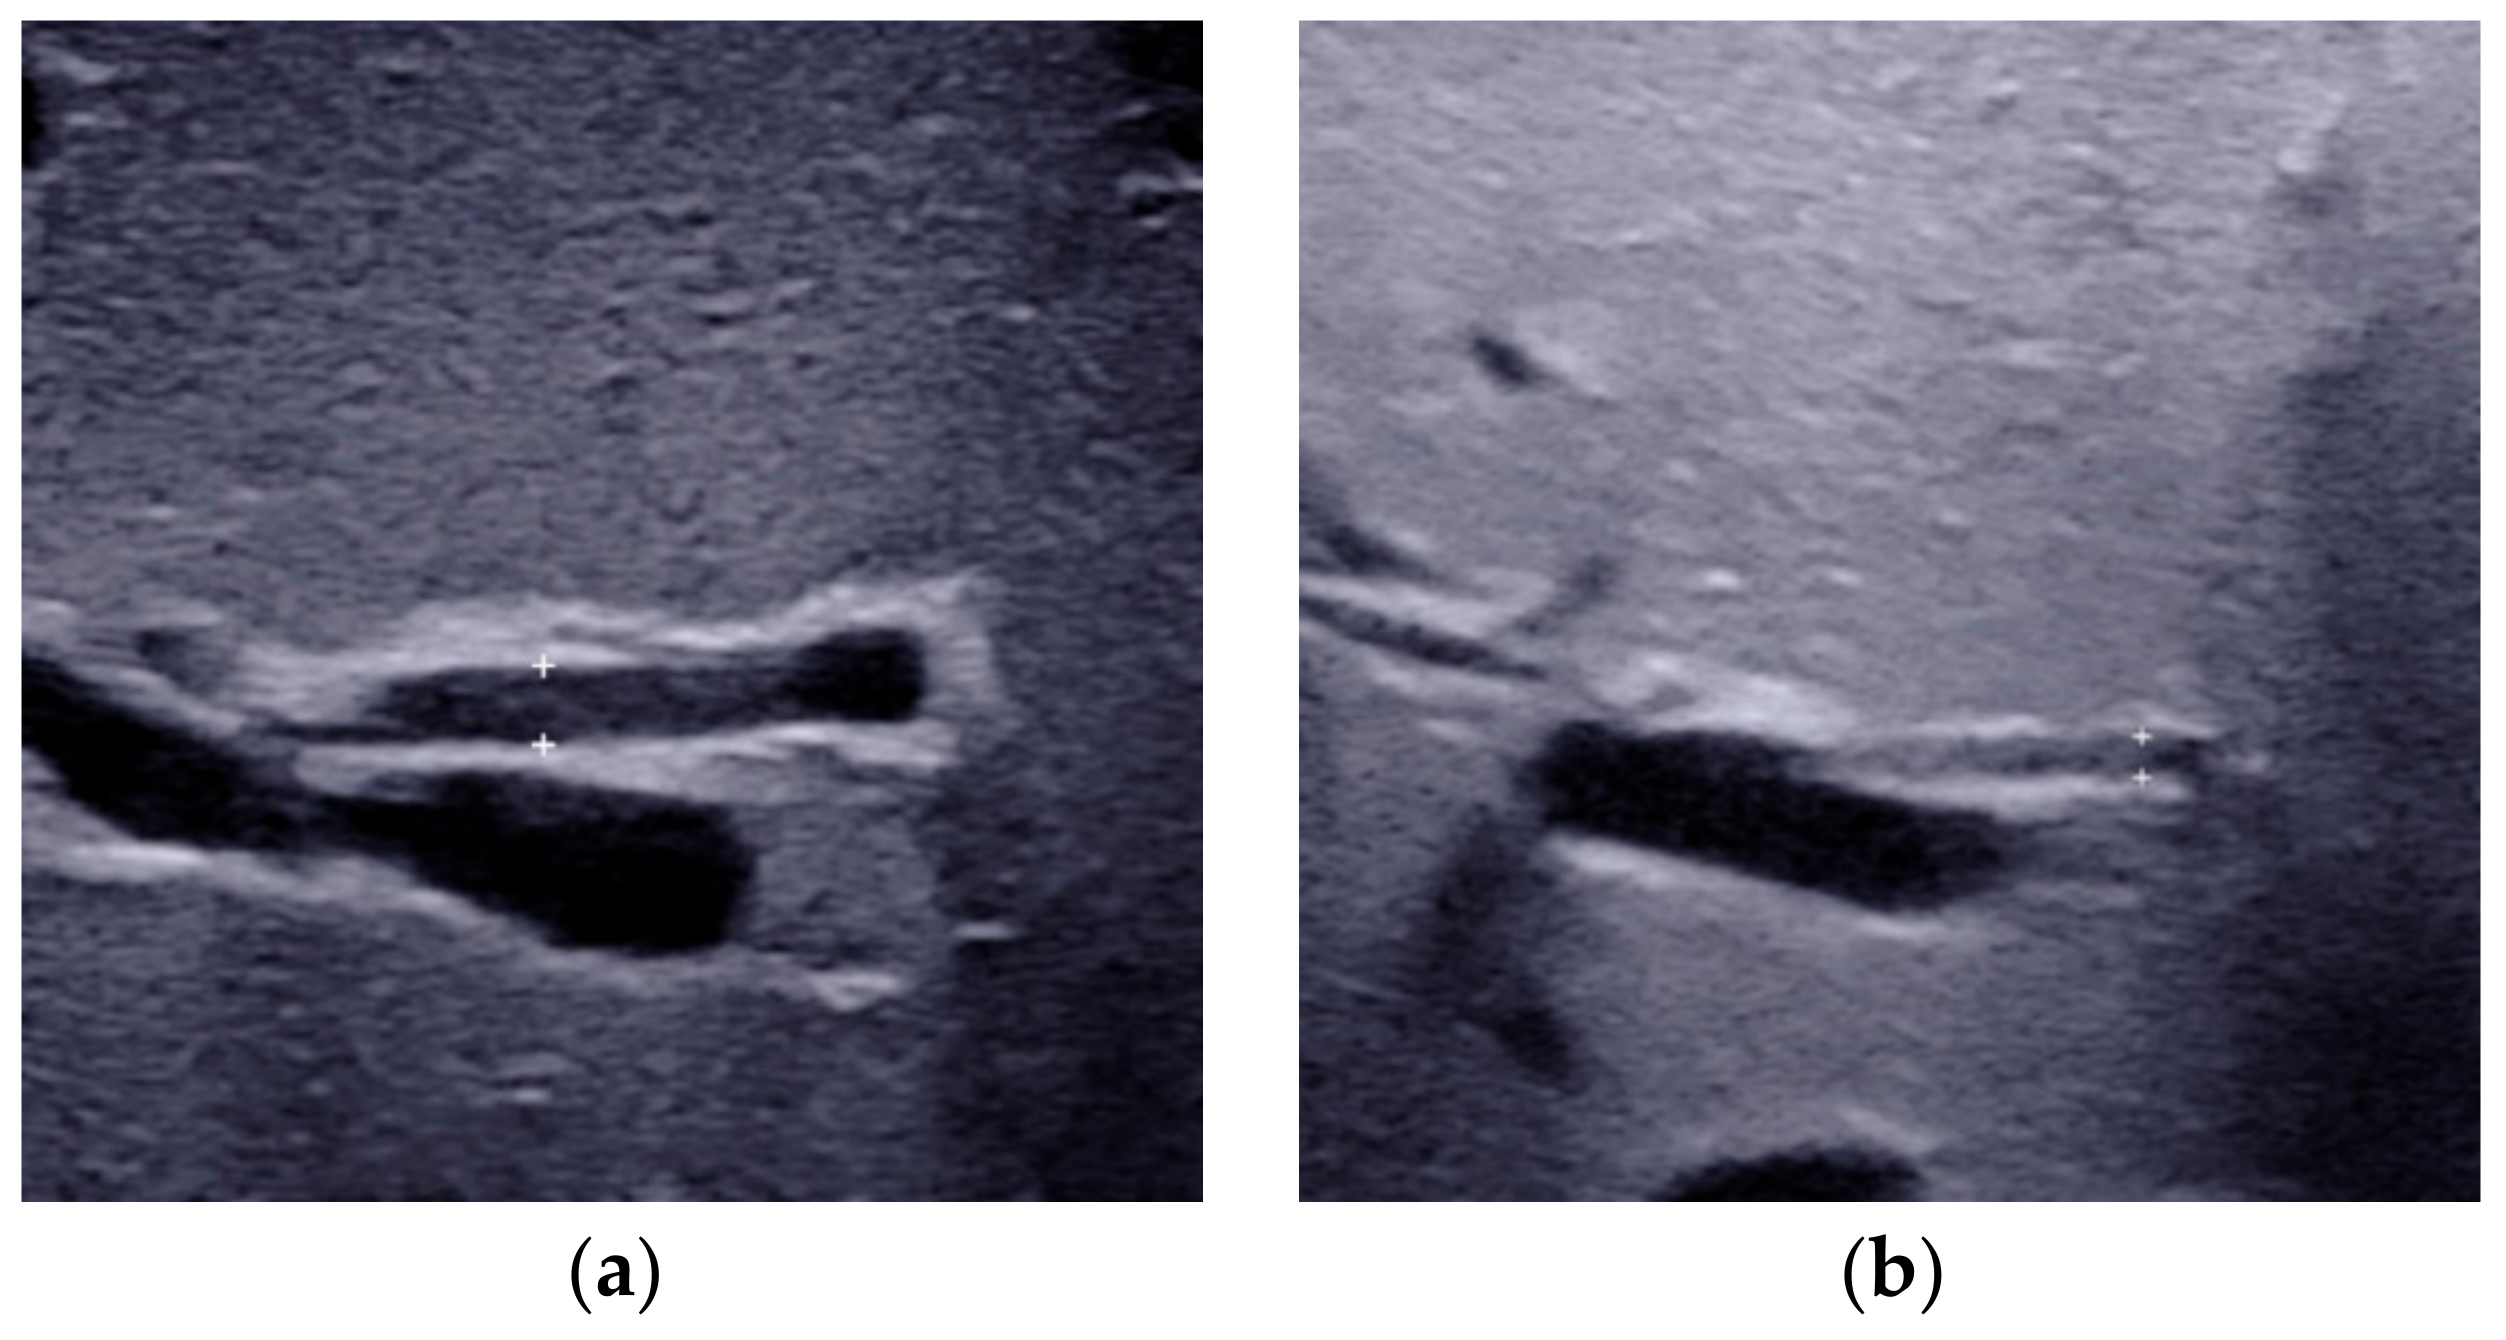

2.5. Other Helpful US Features

- Kim, W.S.; Cheon, J.-E.; Youn, B.J.; Yoo, S.-Y.; Kim, W.Y.; Kim, I.-O.; Yeon, K.M.; Seo, J.K.; Park, K.-W. Hepatic Arterial Diameter Measured with US: Adjunct for US Diagnosis of Biliary Atresia. Radiology 2007, 245, 549–555. [Google Scholar] [CrossRef]

| HA diameter | Measured at the level of right proximal HA running parallel to the right portal vein. | 2.1 mm to 2.5 mm | 1.5 mm to 1.9 mm | Not recommended for diagnosis alone |